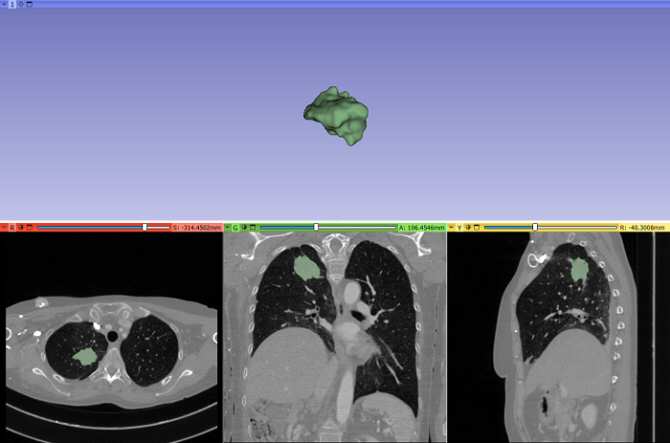

La nueva investigación ha permitido identificar un biomarcador no invasivo para predecir el beneficio clínico duradero de una inmunoterapia contra un cáncer de pulmón. (Imagen: UPM)

Gracias a este estudio, se ha identificado un biomarcador no invasivo para predecir el beneficio clínico duradero de la inmunoterapia, basado en la integración de datos radiómicos y clínicos monitorizados, durante los primeros meses de tratamiento con anticuerpos monoclonales anti-PD-1/PD-L1, en pacientes con cáncer de pulmón no microcítico avanzado.

La identificación de biomarcadores predictivos no invasivos de la respuesta a la inmunoterapia es crucial para evitar interrupciones prematuras del tratamiento o prolongaciones ineficaces. Un biomarcador se utiliza a veces para determinar la respuesta del cuerpo a un tratamiento para una enfermedad o afección.